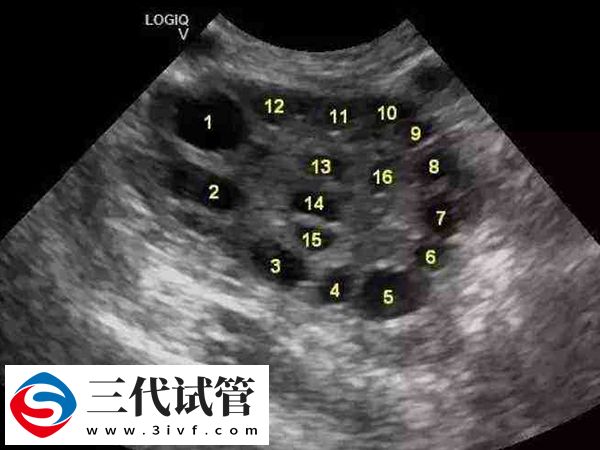

然而要注意,具体的取卵时间是因人而异的,但通常卵巢内至少有1~2个卵泡直径≥18mm,或2~3个直径≥17mm时便可注射破卵针(HCG或Lupron),35个小时之后,专家会进行全麻处理,然后在B超的引导下将取卵针伸进盆腔至卵巢的位置,将卵子取出。只需要15-20分钟就能完成,女性不会有任何的疼痛感,十分安全。

在取卵之前,试管专家会通过B超全程跟踪监测卵泡的发育情况,并且观察女方对药物的反应程度,如有问题会及时调整药量,可以有效避免卵巢过度刺激、腹水、多囊等不良症状的发生,确保女性身体健康,也可以达到非常理想的促排效果。